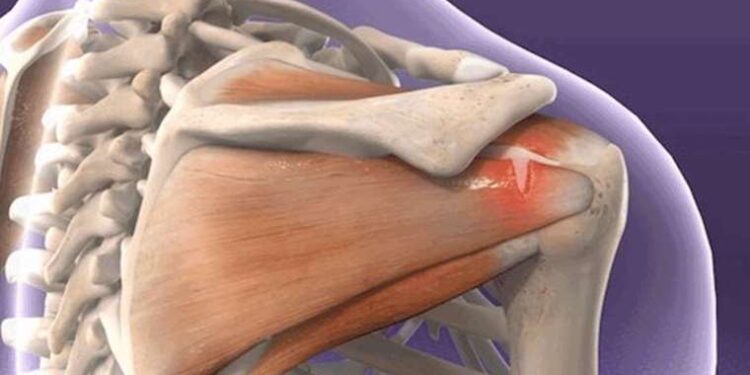

Günlük hayatı etkileyerek hareket kısıtlılığına neden olan omuz eklem ağrıları, altında tendon ve kapsül yırtıkları sorunlarını barındırabiliyor. Tedavi edilmeyen yırtıklar ise uzun vadede eklemde kireçlenme ve fonksiyon kayıpları ile sonuçlanabilir.

Uzun süren omuz eklem ağrılarının altında yatan sebeplerden bazılarının tendon ve kapsül yırtıkları olabileceğini belirten Op. Dr. Balcı, “Sadece ödem ile giden problemlerde lokal enjeksiyon, fizik tedavi, ilaç tedavisi uygulanabildiği gibi bazı yırtıklarda daha ileri seviye tetkikler yapılabilir. Özellikle emar (MR) gibi bir tetkikle bazı yırtıklar tespit edildiğinde uzun vadede kireçlenme, mevcut yırtığın artması ve daha problemli bir eklem sorunuyla sonuçlanmaması adına tetkik sonrasında uygun vakalarda kapalı yöntemle omuz artroskopisi ile müdahale edilerek bu yırtıklar başarıyla tedavi edilebilmektedir” dedi.

Tedavi edilmeyen yırtıkların doğurabileceği sonuçlar ve tedavi yönteminden bahseden Op. Dr. Balcı, “Kapalı yöntemle omuz artroskopisi (kapalı omuz ameliyatı), yırtığın tipine bağlı olmak üzere 1- 1 buçuk saat aralığında sürmektedir. Hasta, ameliyat sonrası 1 gün hastanede kalıyor. Daha sonrasında da yine yırtığın tipine bağlı olarak 3 ila 6 hafta arasında askılı ya da fizik tedaviyle geçen bir iyileşme süreci oluyor. Eğer yırtıklar tedavi edilmezse, uzun vadede mevcut yırtıkların artmasıyla beraber eklemde kireçlenme ve fonksiyon kayıpları ile sonuçlanabilmektedir” diye konuştu.